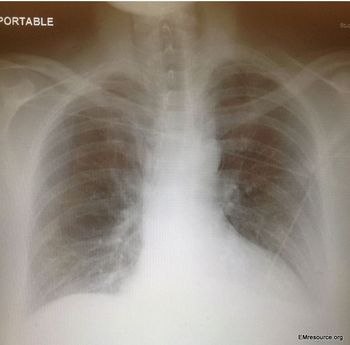

Two hours earlier the patient had vomited to dislodge food stuck in his throat. This had been effective in the past but had never produced blood. Chest and epigastric pain worsened when he lay down.